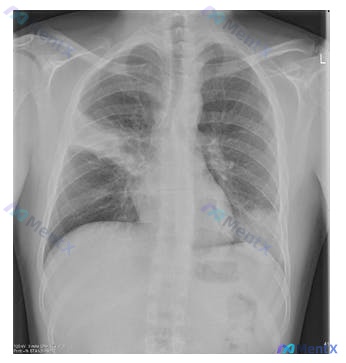

整理了一个很有警示意义的病例,关于高危宿主的复发性肺炎,最后还落到了「药物作用机制」这个核心考点上。 --- 先看完整病例信息 患者:54岁男性,建筑工人,与10人同住。 主诉:咳嗽、胸痛、气促1周,加重伴发热2天。 现病史:2个月前有类似发作史,当时用抗生素治疗(具体不详)。 既往史:糖尿病5年,...